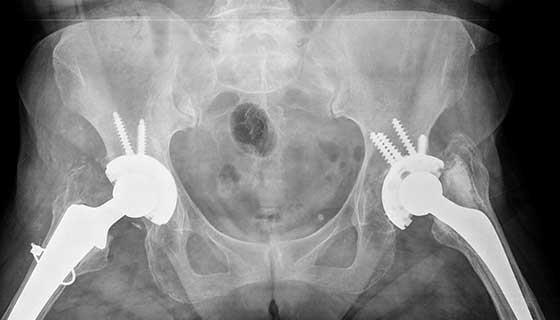

A hip replacement surgical procedure is a medical method to replace a damaged or worn-out hip joint with an artificial one. This surgical treatment objectives to relieve aches, enhance mobility, and enhance the general fine of existence for individuals dealing with hip problems.

● Type of Implant: Discuss the sort of implant a good way to be used in your surgery. There are diverse substances and designs to be had, so it’s critical to choose the only one that fits you fine.